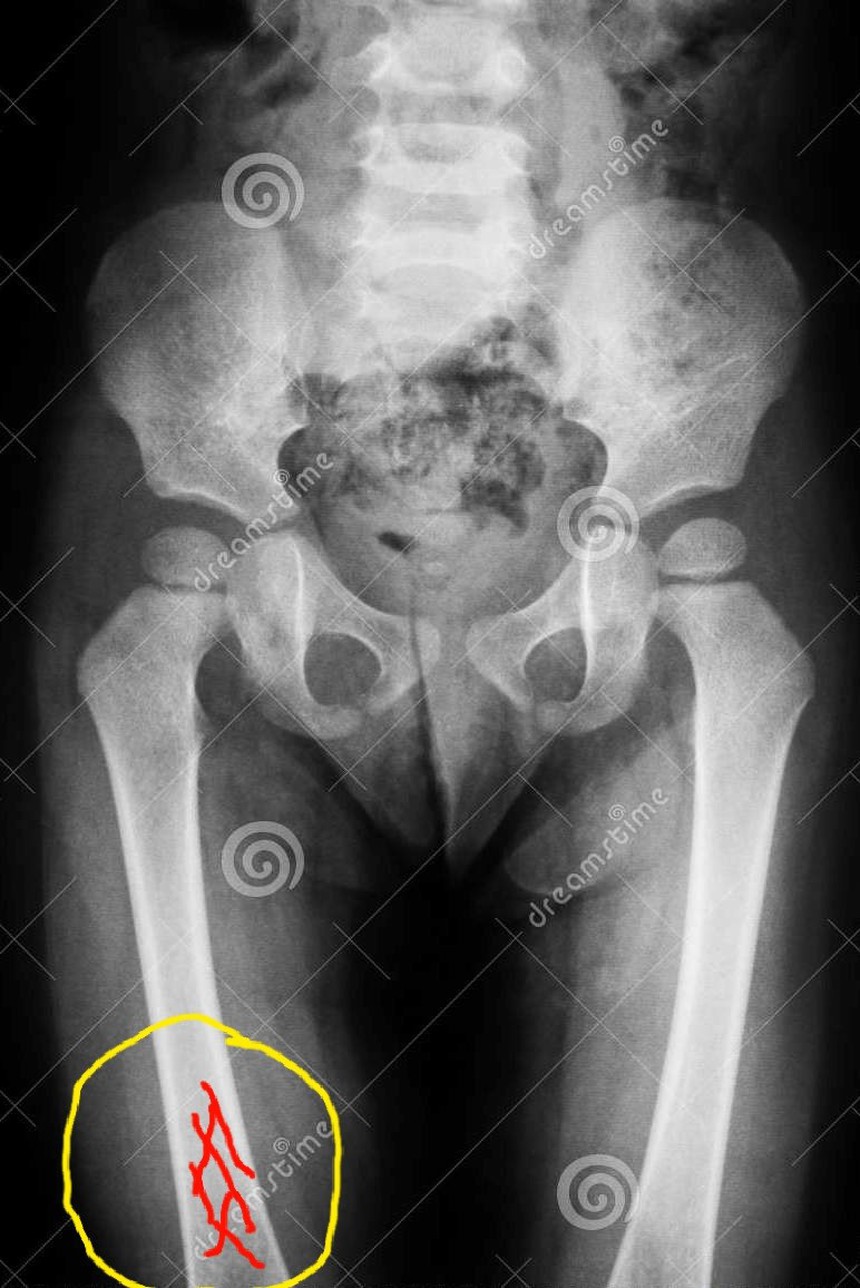

Hình minh họa vị trí xương bị rạn nứt trong quá trinh phục hồi, trường hợp bộ xương người đàn bà chết do tại nạn khai quật ở Xóm Rền 2005

3. Điều đáng chú ý là màu xám xanh tụ máu và nhiều vết rạn trên xương đùi phái phía trên gối. Đối chiếu với sưu tập xương mang thương tích hiện lưu tại bảo tàng Phạm Huy Thông, dễ nhận ra vùng tụ máu là kết quả chảy máu trong ngấm vào xương do bầm dập. Các rạn xương xuất hiện nhiều trên xương người cổ có cả nguyên do bị đất nén và rạn nứt tự nhiên. Nhưng trên phần đùi phải của chủ nhân ngôi mộ này các vệt rạn nứt có dấu hiệu sùi xương của một vết gãy, rạn trên cơ thể người vẫn còn sống.

Khi học tập và nghiên cứu ở châu Âu, tôi đã rất ấn tượng với những sọ thời đại đá mới được mổ khoét sau đó đạy lại. Những sọ chủ nhân chết ngay sau ca mổ để lại vành "nắp đậy" rời ra rất sạch sẽ. Trái lại một số "nắp đậy" mà chủ nhân còn sống tiếp tục có dấu hiệu sùi xương hàn kín vết nối, như dạng bó bột xương gãy hiện nay vậy. Hiện tượng hai rìa các đường nứt, rạn xương trên đùi phải của người phụ nữ 3.500 năm trước ở Xóm Rền cũng vậy, chúng đang mọc tiếp để tự hàn, chống chọi với vết thương. Tuổi của quá trình đùn xương trên bộ xương này được các chuyên gia xương cốt người đánh giá là chỉ chừng vài tháng thì dừng. Có lẽ vết thương nhiễm trùng đã gây ra cái chết của người phụ nữ xấu số.

Qua kết quả nghiên cứu ứng dụng phương pháp khoa học hình sự có thể kết luận người phụ nữ Xóm Rền có thể đã bị tai nạn do một vật nặng (gỗ hay đá) đè vào phần đùi trên gối bên phải. Vật nặng đó đã khiến xương đùi bị rạn nứt, tụ máu chứ không gãy. Bà đã được cứu chữa và sống tiếp môt vài tháng rồi qua đời, có thể do nhiễm trùng vết thương.